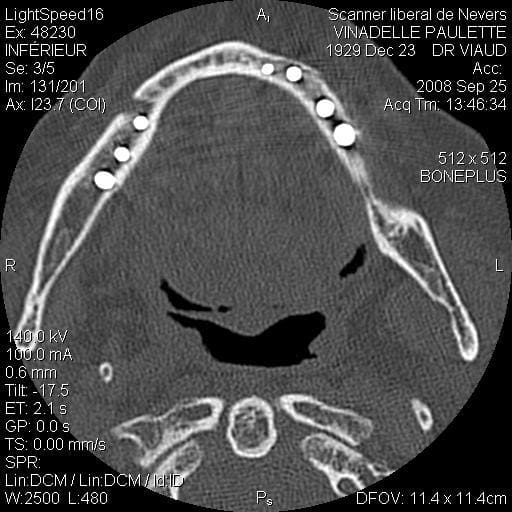

Je suis désolé mais le seul problème que j’ai eu sur un maxillaire inférieure (celui que j’ai mis en photo d’ailleurs) c’est une rupture de la table interne en 33 34 (suite à un mouvement inopportun de la patiente, ce que j’aurais du prévoir) j’ai repris le cas 3 mois plus tard et no problème.

scan te montrant la façon dont je contourne les obstacles